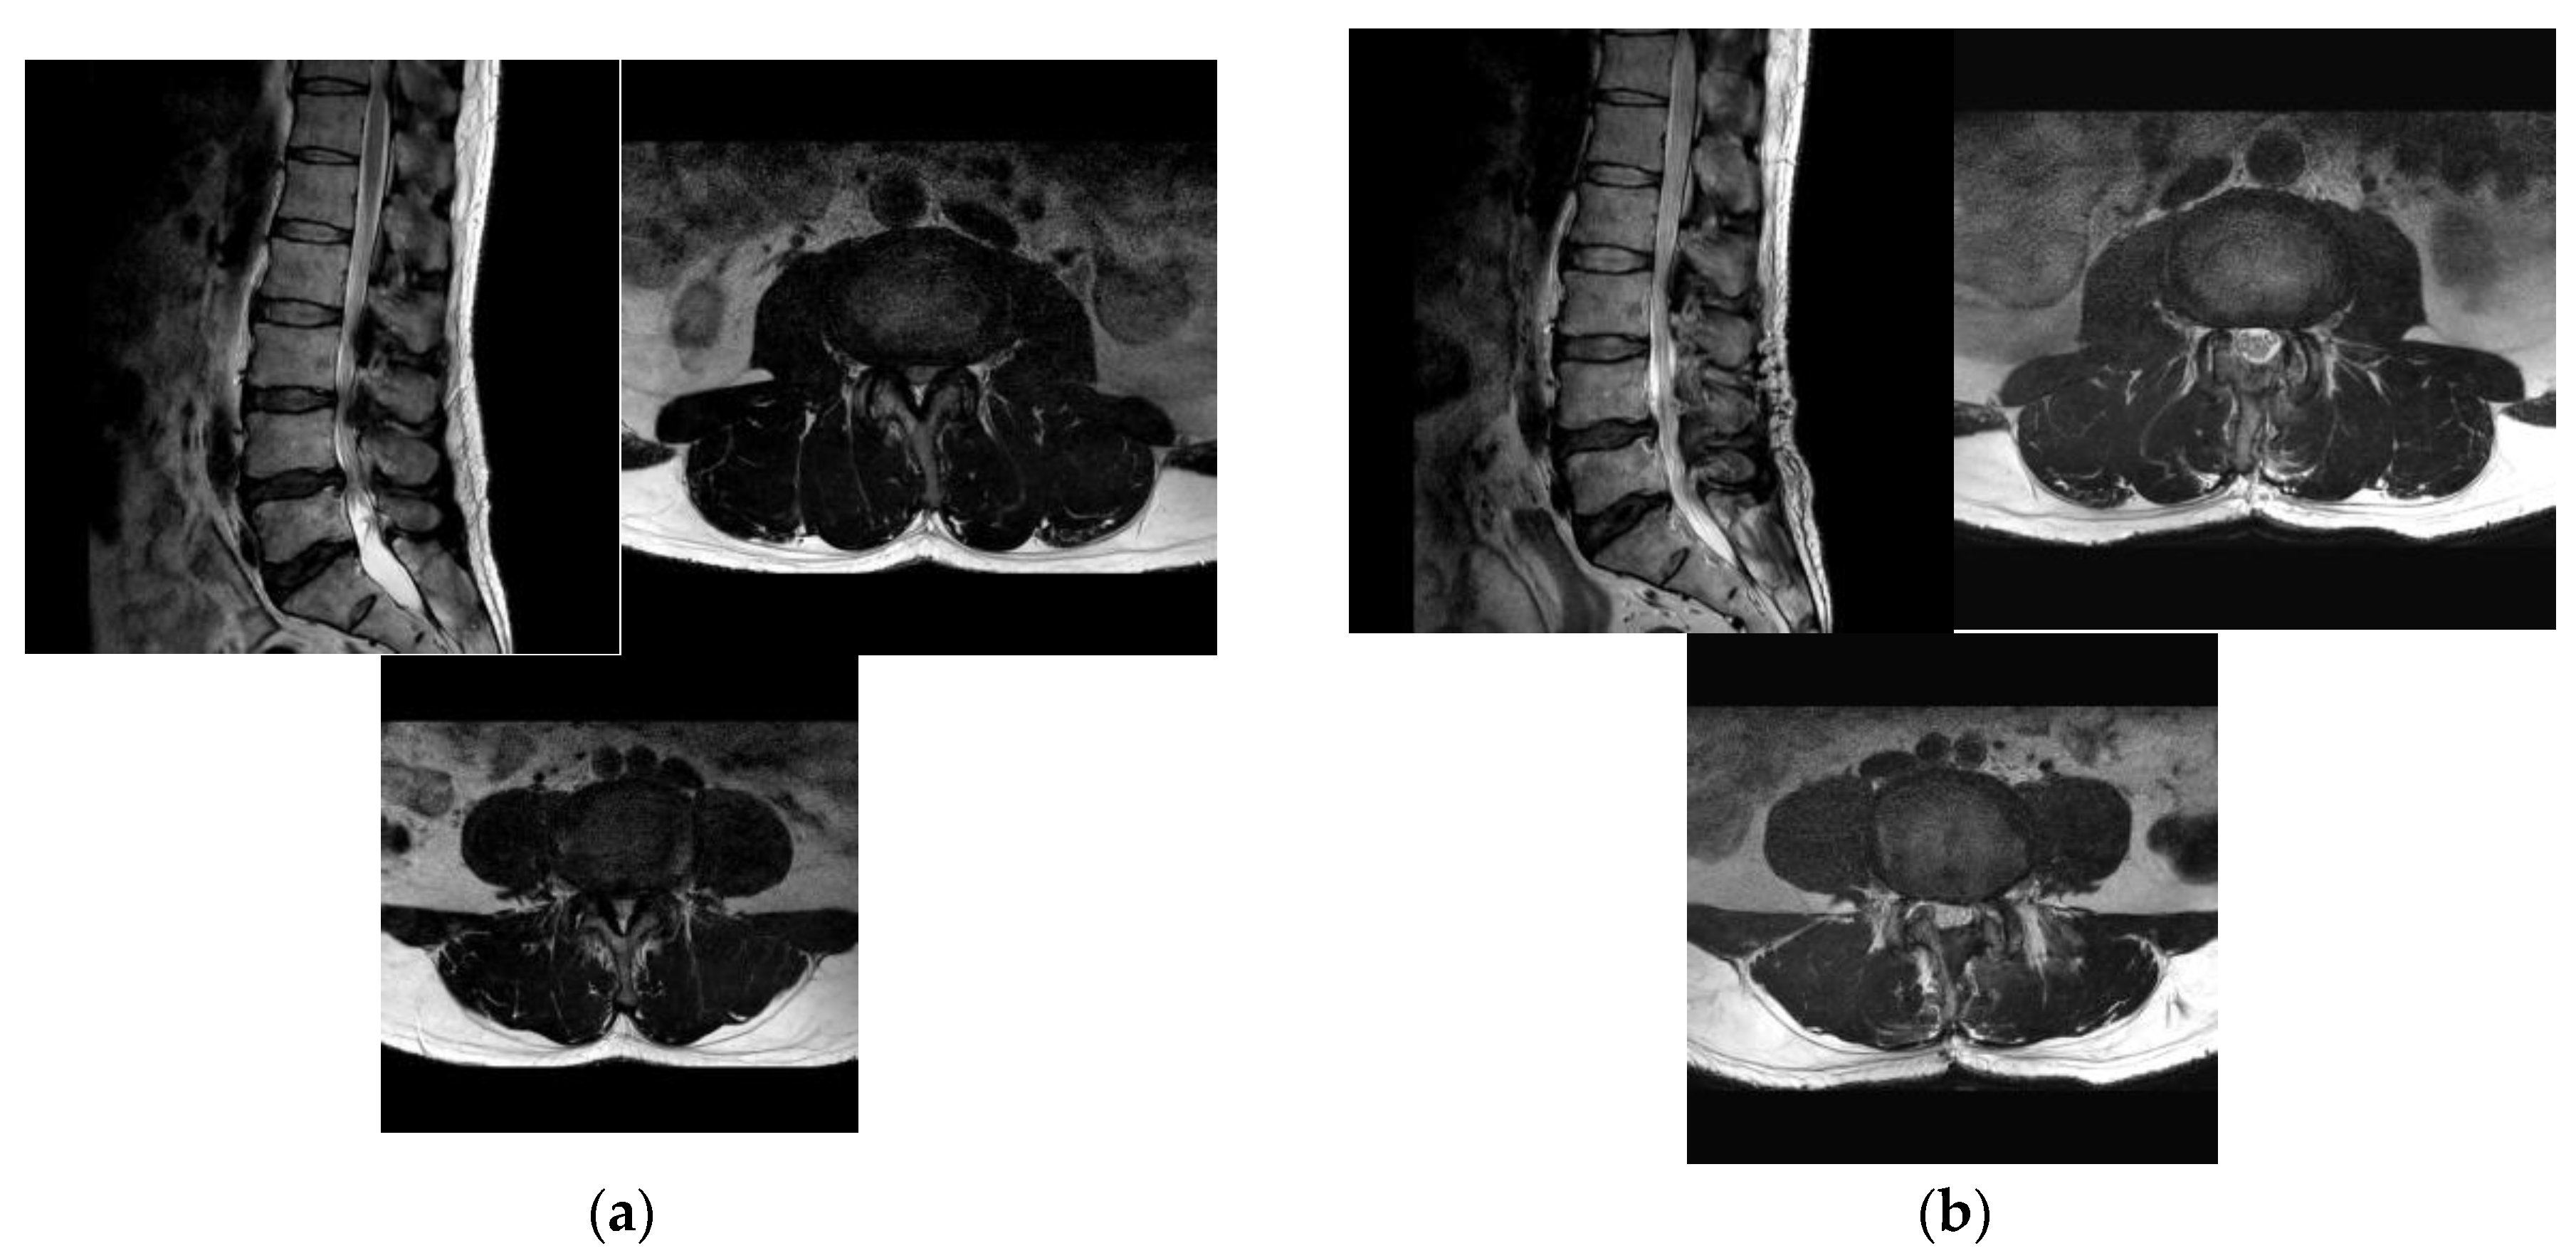

3.3. Radiologic Outcome Evaluation